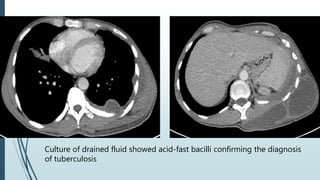

20 yrs. male Complaints of

- Mass on posterior aspect of left back for 2

months.

- Low grade fever for same duration

Culture of drained fluid showed acid-fast bacilli confirming the diagnosis

of tuberculosis

20 yrs. maleComplaints of - Mass on posterior aspect of left back for 2 months. - Low grade fever for same duration

Culture of drainedfluid showed acid-fast bacilli confirming the diagnosis of tuberculosis